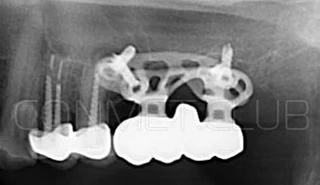

Первый вывод к которому мы пришли, это то, что для данных конструкций имплантатов сохранять внутренний интерфейс с шестигранником и конусом Морзе нецелесообразно из-за ограничения возможностей современной 3D печати титана. Кроме того, техническая обработка после 3D печати такого интерфейса представляет значительные трудности и ведет к неоправданному увеличению цены. Поэтому пришли к единодушному мнению, что лучший вариант-это опорные элементы полностью повторяющие абатменты-мультиюниты.

Второй, и наверное главный вывод-решение - моделированием и конструированием индивидуальных, субпериостальных имплантатов должен заниматься инженер-конструктор с большим опытом в медицине и знаниями индивидуальной анатомии челюстно-лицевой области на уровне хорошего хирурга. При этом все-равно должно осуществляться тесное и постоянное взаимодействие с хирургом, который будет проводить операцию.

Посмотрите на приведенные выше работы и вы обратите внимание, что перфорации в теле имплантатов подчиняются скорее "художественным" принципам нежели биомеханическим. Поэтому уже в 2018 году не только изготовление, но и конструирование имплантатов было целиком передано сотрудникам Конмет. Это в значительной степени повысило качество самих имплантатов, но по вполне понятным причинам (таких грамотных инженеров-конструкторов по определению не может быть много) резко удлинились сроки изготовления. При определенных случаях, когда после удаления зубов кость еще не окончательно закончила ремоделировку, срок с момента КТ по которому моделируют субпериостальный имплантат, до операции может носить критический характер. Т.е., чем дольше время изготовления, тем больше вероятность того, что имплантат не полностью будет соответствовать рельефу подлежащей костной ткани.

Посмотрите на небольшом клиническом примере новый подход к конструированию имплантата по сравнению с имплантатами описанными в начале этой статьи.

Результаты проведенных в 2017-2018 году операций субпериостальной имплантации показали их высокую эффективность, очень быструю адаптацию пациентов к новым зубам и отсутствие послеоперационного болевого синдрома. Интересной особенностью является труднодиагносцируемая, но точно присутствующая микроподвижность имплантатов спустя 6-12 месяцев. Учитывая данную особенность надо категорически избегать объединения субпериостальных имплантатов с естественными зубами или внутрикостными имплантатами!